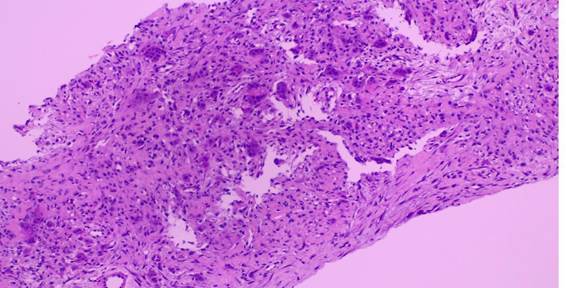

Em nova análise histopatológica, descreve-se um tumor composto por proliferação de padrão fusocelular de pleomorfismo discreto, contendo células gigantes multinucleadas, focos de extravasamento de hemácias e áreas de formação de osteoide (Figura 1). Não havia focos de necrose, o índice mitótico era baixo (1 mitose/10 campos de grande aumento), não sendo identificadas mitoses atípicas.

Figura 1. Proliferação de padrão fusocelular contendo células gigantes multinucleadas (microscopia óptica, hematoxilina-eosina, 100x)